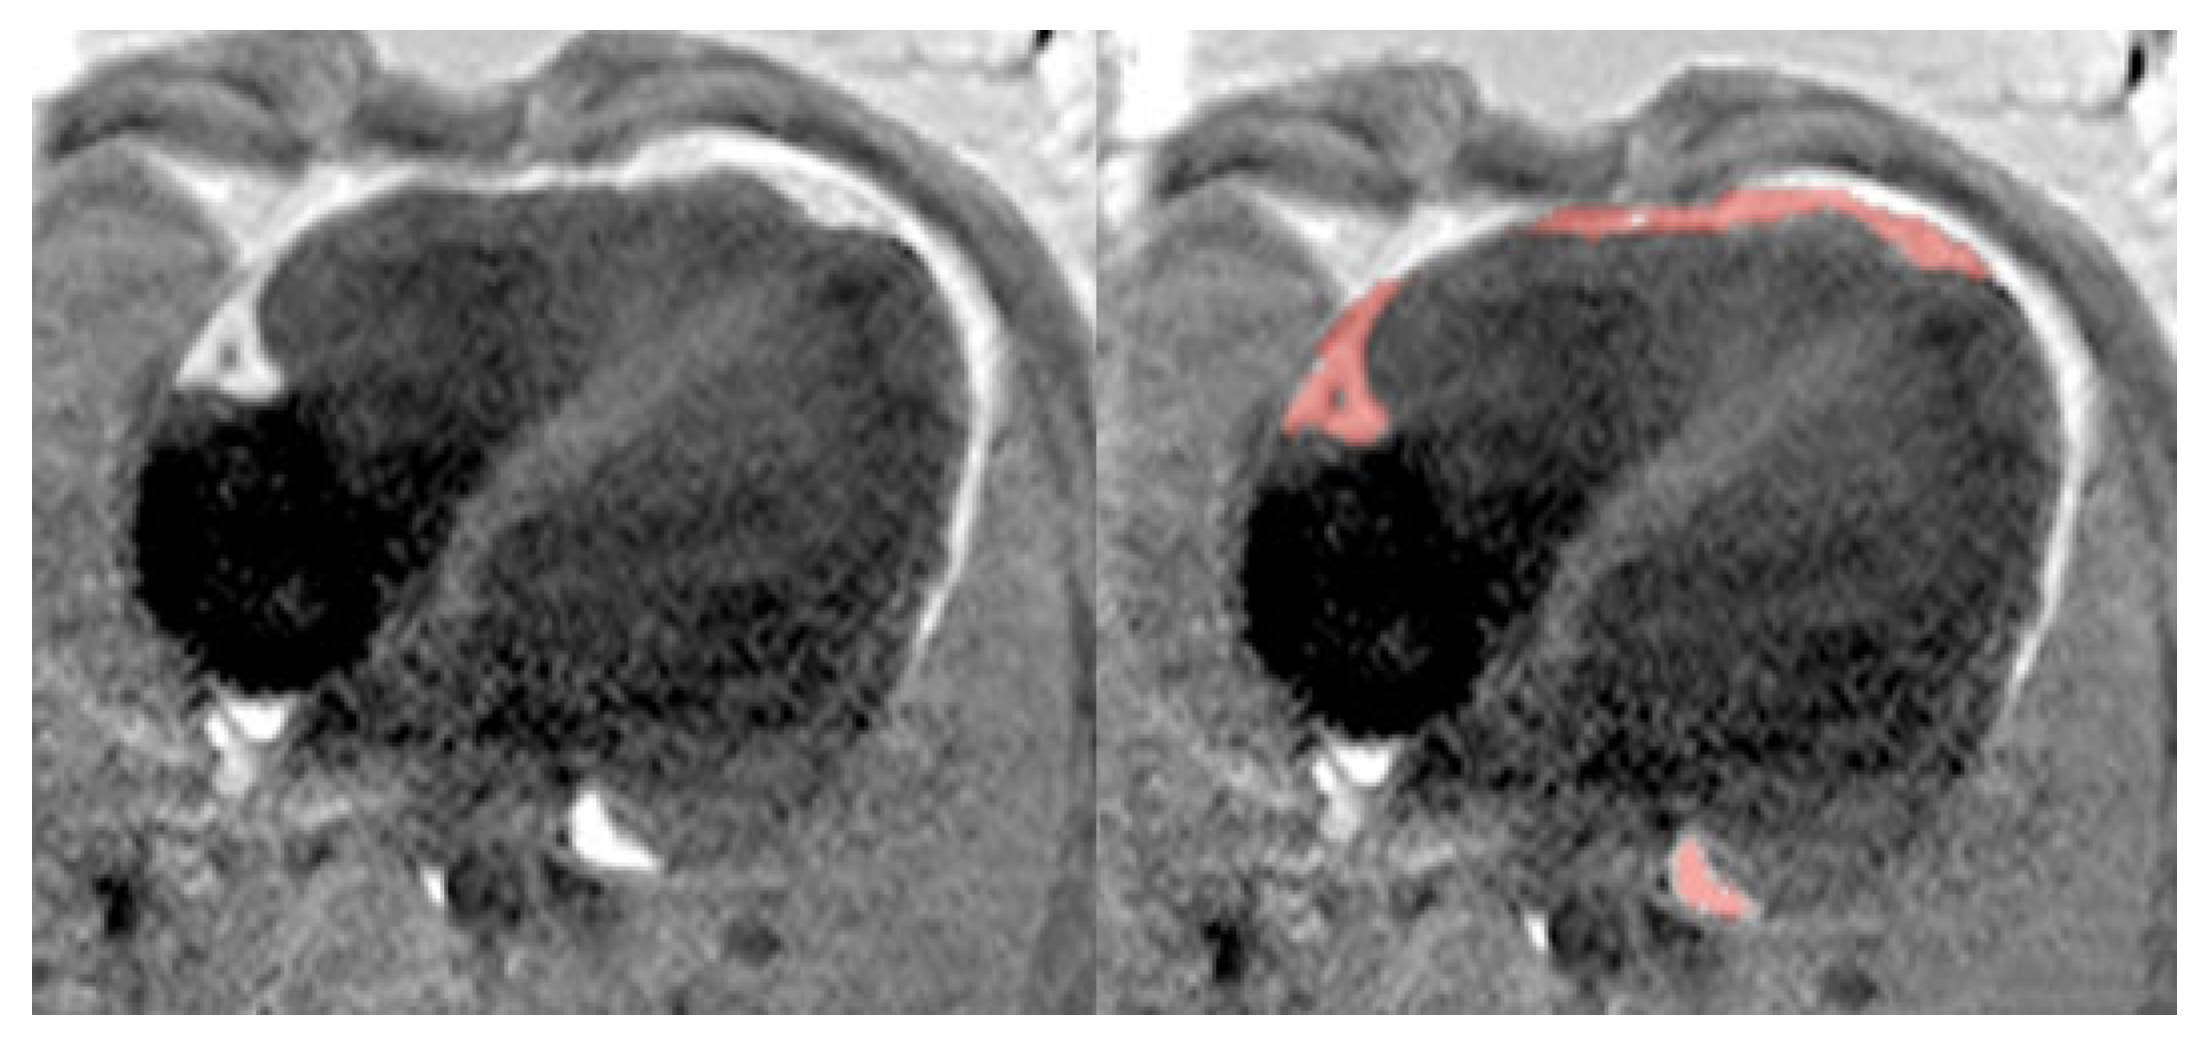

2.2.6. Magnetic Resonance Data Analysis